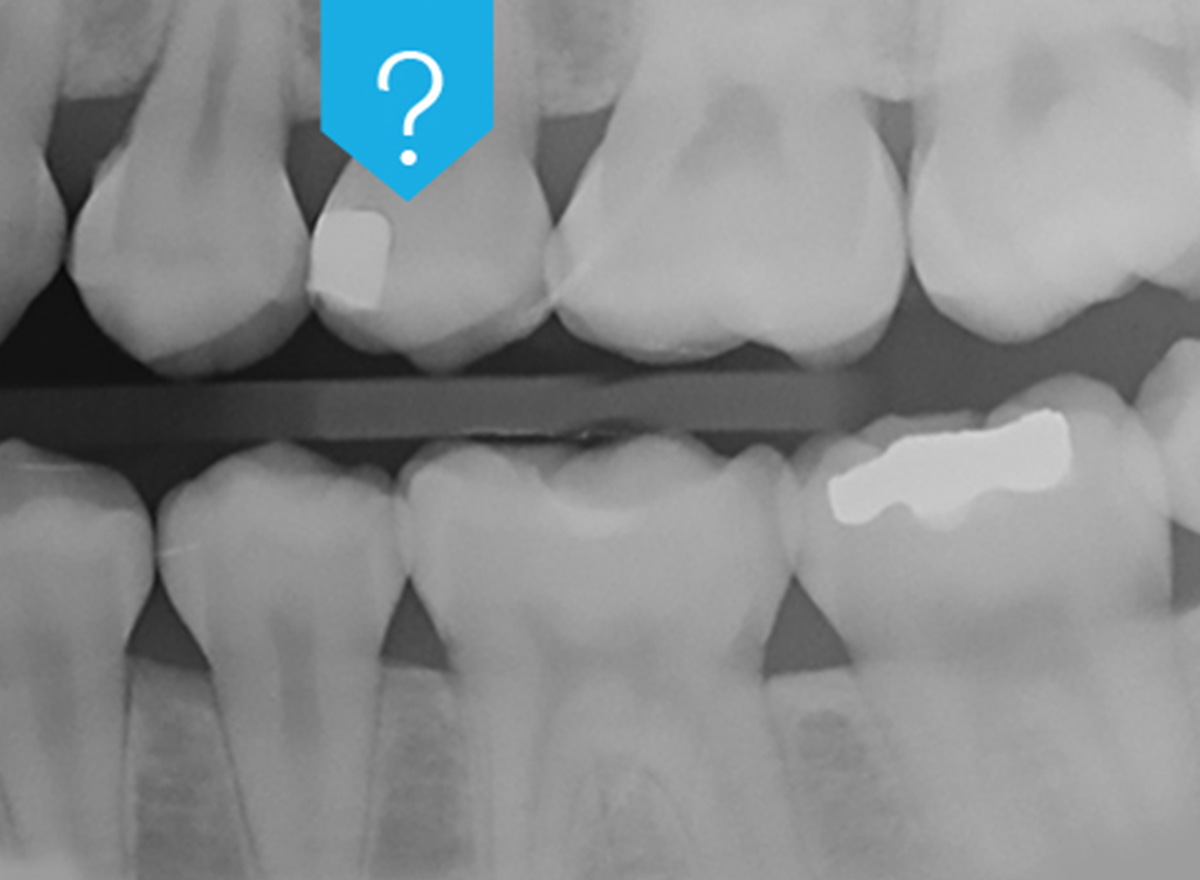

Radiolucency under an existing restoration can lead to misdiagnosis. Help cut down on unnecessary restorative rework by choosing a radiopaque bonding adhesive.

A radiolucent adhesive makes it impossible to differentiate between adhesive pooling and secondary caries, marginal gaps or voids beneath the restoration, particularly in difficult-to-inspect areas. Very experienced practitioners may try to distinguish between secondary caries and the adhesive layers by taking the morphology of the radiolucency into consideration, but it remains an educated guess with no guarantee. To be 100% sure, and to avoid legal problems, many practitioners prefer to replace the restoration entirely, which may end up being completely unnecessary. In these cases, radiopacity is clearly a desirable property for dental adhesives.